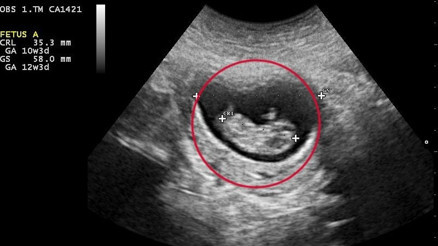

Gebelik kesesi, bebeğin varlığının en önemli kanıtı olarak çiftler için merakla beklenen bir oluşumdur. Hamilelik süresi boyunca bebeğin geliştiği yer olan gebelik kesesi ne zaman, kaçıncı haftada gçrülür? İşte gebelik kesesi hakkında merak edilenler…

#GebelikGebelik kesesi embriyoyu saran sıvı boşluğuna verilen isimdir. Rahim içerisinde bulunan bu kese embriyonun tanımlanmasından önceki süreçte gebeliğin belirlenmesi için oldukça önemlidir. Gebelik kesesi hamilelik süresince bebeğin gelişimin gerçekleştiği bölge olması sebebiyle oldukça önemlidir. Bazı durumlarda boş gebelik kesesi oluşabilir. Bu durumda kese oluşumu gerçekleşse de embriyo oluşumu yoktur.